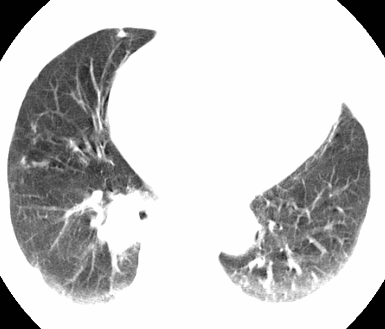

标题: CT26680:肺部右下肺静脉干结节的界定 [打印本页]

标题: CT26680:肺部右下肺静脉干结节的界定

经追查说有支扩咯血病史,但不确定

考虑1、周围型肺癌,2肺静脉畸形,前者可能大,建议增强检查。

考虑1、周围型肺癌,2肺静脉畸形,前者可能大,建议增强检查。支持!

不排除右肺下叶周围型肺癌可能。